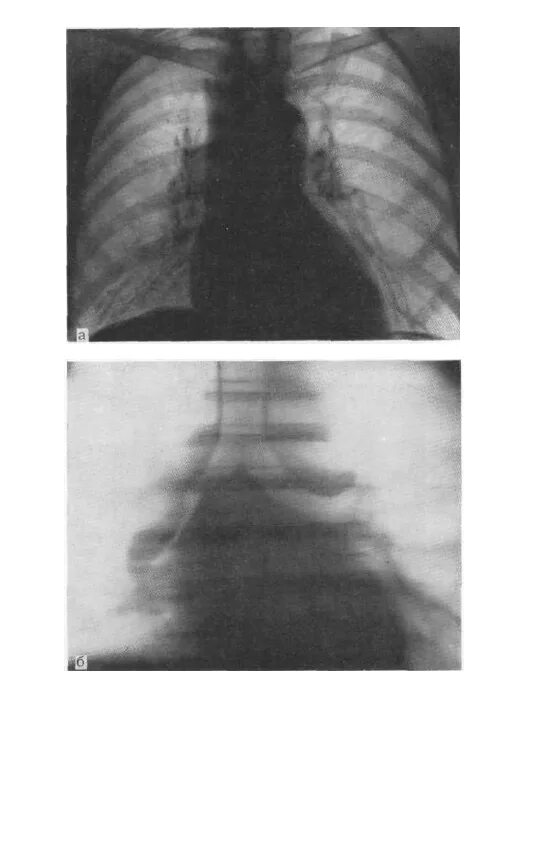

Метастазы в средостении легких